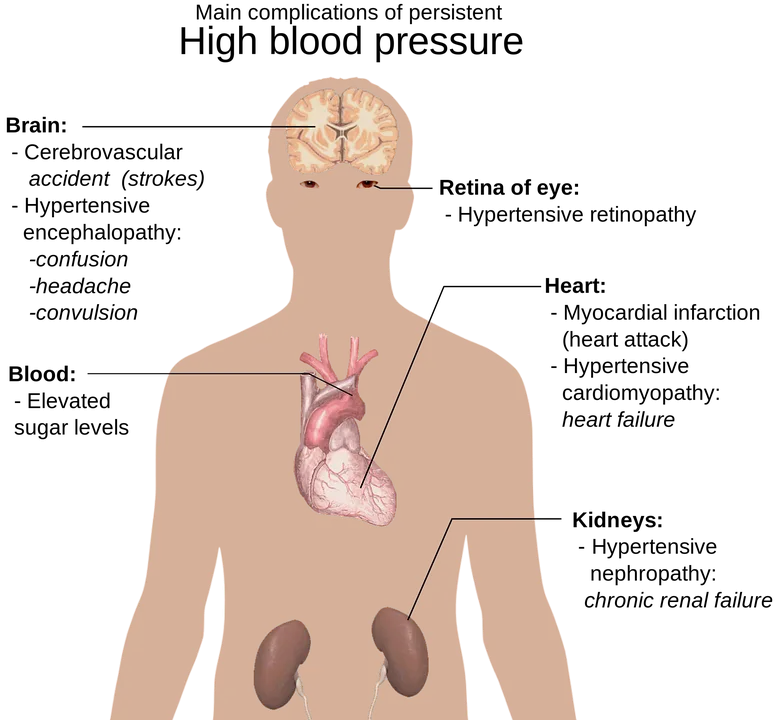

Essas doenças são Dislipidemias, Obesidade Abdominal, Diabetes Mellitus ou intolerância a glicose. Estudos mostram na coexistência desses fatores, associam-se a maior risco de morte súbita, acidente vascular encefálico(AVE), Doença vascular periférica, Insuficiência Cardíaca, Infarto agudo do miocárdio e Doença renal crônica.

Então por isso o controle adequado da pressão arterial se faz necessário, a pressão mantida em níveis elevados já aumenta o risco de complicações, associada a outras comorbidades, aumentam mais ainda.

Estudos americanos consistentes, mostram que a HAS é diretamente responsável por 45% das mortes cardíacas, e 51% das mortes decorrentes de AVE.